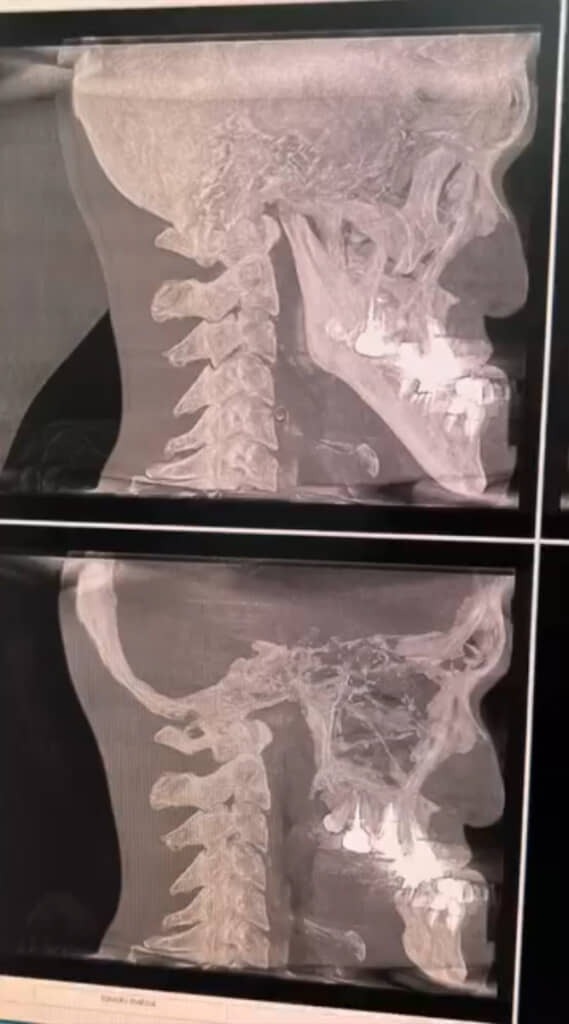

自稱擁有世界最長下巴的日本YouTuber「城之內」,日前決定接受網友提議,去牙科接受X光評估,看看他的下顎骨到底長怎麼樣。X光報告一出來,不只讓城之內本人和醫生大為驚訝,也震撼400多萬網友。

城之內的X光片顯示,他的下巴之所以這麼長,要歸功於他奇異的骨骼結構。牙醫師也很驚訝,表示像他這樣的下顎骨真的非常少見,不只顎骨長度過人,連角度也非常獨一無二。

▲一般人的X光片 (上) 、城之內的X光片 (下)